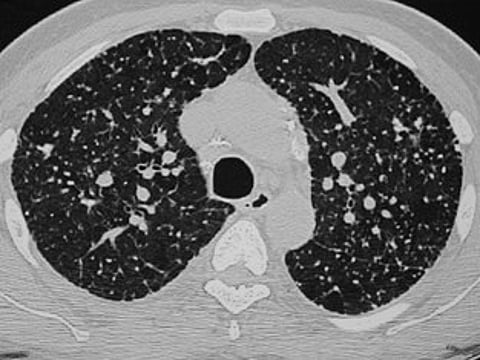

सांगली ः कोरोना रुग्णांची एचआरसीटी करणे काही प्रकरणात आवश्यक ठरत असून त्यात खुलेआम लूट सुरु झाली आहे. कुणीही कितीही दर आकारत आहे. या प्रकरणी राज्य शासनाकडे मोठ्या प्रमाणात तक्रारी दाखल झाल्या होत्या. त्यानंतर आता दिलासादायक बातमी असून राज्य शासनाने एचआरसीटी अर्थात सिटीस्कॅन करण्याचे दर निश्चित करण्यासाठी समिती गठीत केली आहे. पुढील सात दिवसांत पूर्ण अभ्यास करून सिटीस्कॅनचे कमाल दर ठरवण्याचे आदेश दिले आहेत.

याआधी रुग्णालये आणि खासगी प्रयोगशाळांमध्ये आरटीपीसीआर, रॅपीड अँटीजेन आणि रॅपीड अँटीबॉडी तपासण्यांसाठी दर निश्चित केले आहेत. आता एचआरसीटी करण्यासाठीचे दरही निश्चित होती. राज्य आरोग्य हमी सोसायटीचे मुख्य कार्यकारी अधिकारी सुधाकर शिंदे यांच्या अध्यक्षतेखाली सायन हॉस्पिटलच्या रेडीऑलॉजी विभागप्रमुख अनघा जोशी, जेजे रुग्णालयाचे अधिष्ठाता आणि आरोग्य सेवा आयुक्तालयाचे संचालक अशा चार जणांची समिती असणार आहे. रुग्णालये आणि एचआरसीटी केंद्रांशी चर्चा करून हे दर निश्चित केले जाणार आहे. तसे आदेश राज्य शासनाचे प्रधान सचिव डॉ. प्रदीप व्यास यांनी दिले आहेत.